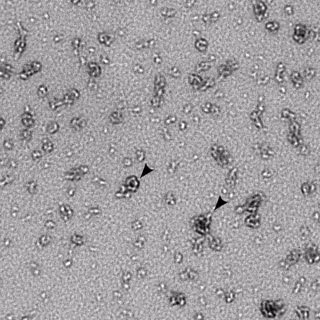

La infección por clamidia incrementa el riesgo de infertilidad

Clamidia

FLICKR/NIAID